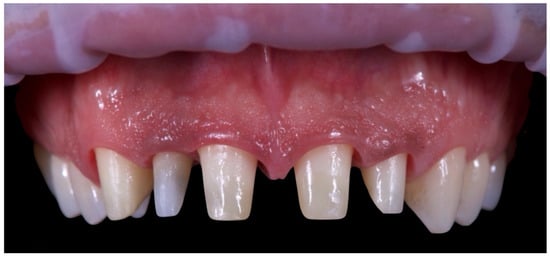

A 39-year-old male patient presented for prosthetic rehabilitation of the anterior maxillary region, primarily motivated by aesthetic concerns and periodontal health improvement. The patient reported a history of smoking (10–15 cigarettes per day since he was 18 years old) and had been diagnosed with localised stage III, grade B periodontitis. Even if the defect is mostly horizontal and localised to the II sextant, stage III was defined due to the bone loss extending to the middle third of the roots and the probing depth is ≥6 mm in this sextant. Moreover, smoking represents a risk factor able to classify the case as grade B. Initial clinical and radiographic evaluation (Figure 1) revealed the absence of all four third molars, the presence of conservative restorations on teeth 1.6, 3.7, and 4.6, and evidence of horizontal alveolar bone resorption in the regions corresponding to teeth 1.4 and 2.3. A conoid morphology was noted in the upper left lateral incisor.

Figure 1. Initial radiographic assessment.

The initial aesthetic evaluation revealed a 7 mm incisal display at rest, a flat incisal edge morphology, a high smile line, and a smile width encompassing ten teeth with normal buccal corridors. The facial midline was aligned with the interincisal midline, although a diastema was observed between teeth 1.1 and 2.1 (Figure 5).

Figure 5. Clinical image demonstrating coincidence of the facial midline with the maxillary interincisal line. A midline diastema is evident.